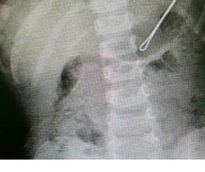

نجح الفريق الطبي بوحدة مناظير الجهاز الهضمي بمستشفى الولادة والأطفال في بريدة بالسعودية، باستخراج قطعة حديدية "مثبت للشعر" من معدة طفل يبلغ من العمر عامين. وبحسب موقع "العربية نت"، فقد ذكر رئيس وحدة مناظير الجهاز الهضمي بالمستشفى الدكتور عبدالعزيز الحربي، بأنه تم إجراء العملية بنجاح والطفل يتمتع بصحة جيدة، منبهاً الأسر إلى ضرورة الاهتمام بمتابعة الأطفال وما يضعون في أفواههم حتى لا يتعرضوا للاختناق في حال لم يتم تدارك الأمر، مشيراً إلى أن المستشفى شهد تطورا في جراحات المناظير والجهاز الهضمي مما يسهم في تقديم أفضل خدمة علاجية للمرضى.